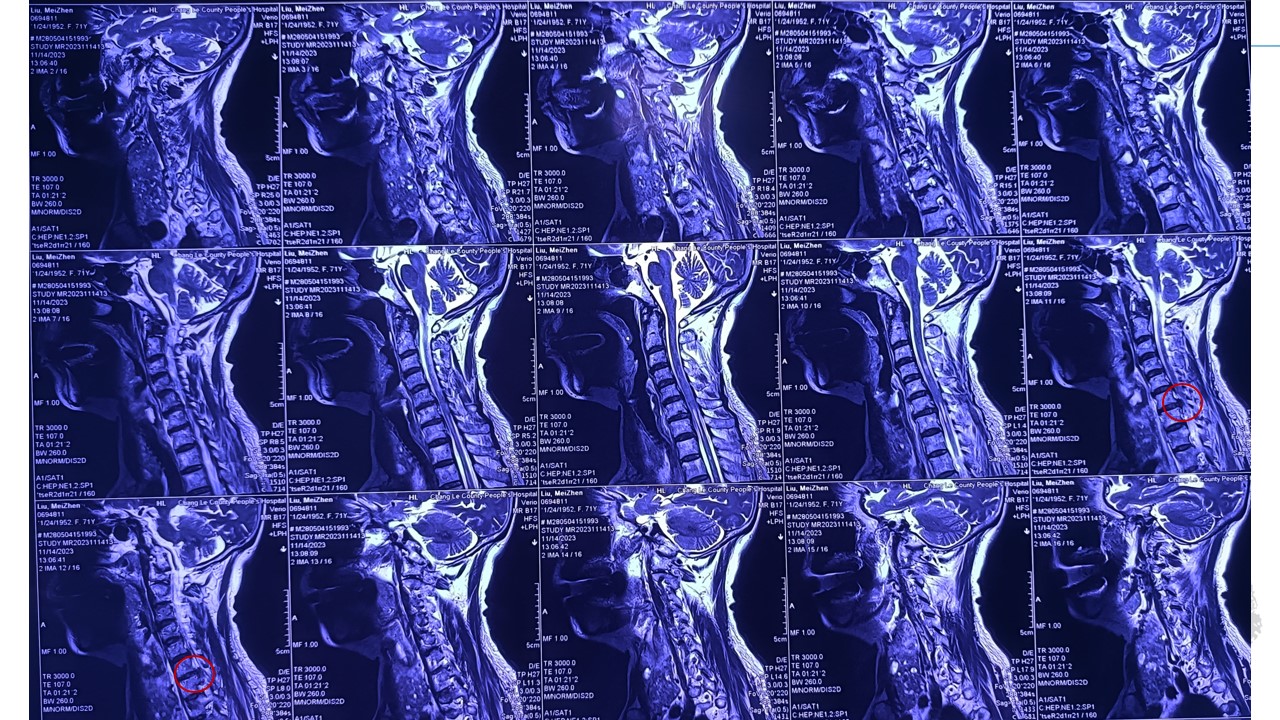

脊柱内镜下颈椎后路椎间孔减压髓核摘除术1例-山东大学齐鲁医院神经外科脊柱脊髓团队